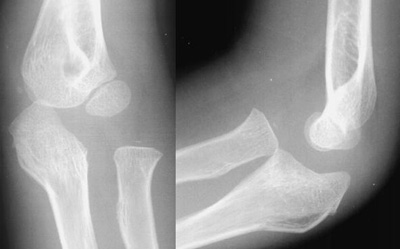

An abnormal radio-capitellar line

On both views the radius fails to bisect the capitellum indicating an obvious radial head dislocation. Also note the anterior and posterior fat pads, as well as the obvious olecranon deformity. A radial head dislocation with an olecranon fracture is called a Monteggia injury.